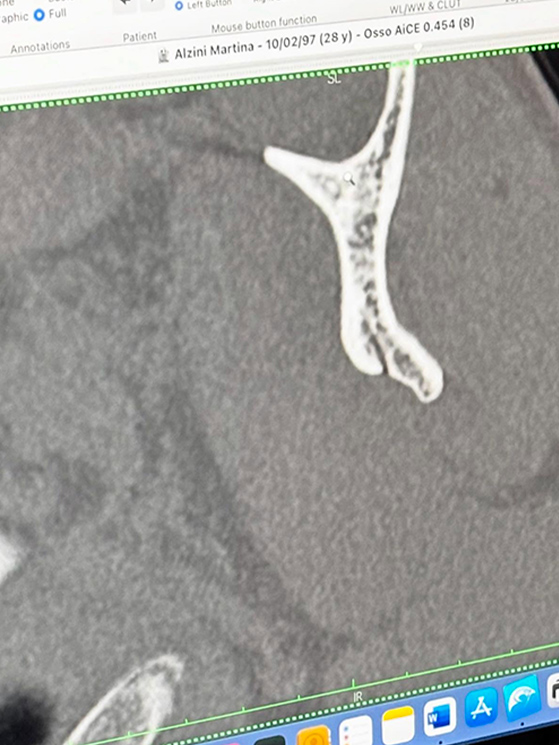

In 28 anni non mi ero mai rotta nulla e ho capito che era un dolore mai provato prima, che non era un fatto solo di botte. All’inizio hanno parlato di una micro frattura. Però l’ortopedico ha visto bene tutto e ha parlato di una frattura più seria. Ho pubblicato la foto della lastra per far capire che comunque non è una cosa lieve e che starò un bel po’ fuori. Per assurdo, se mi fossi operata subito, avrei fatto prima.